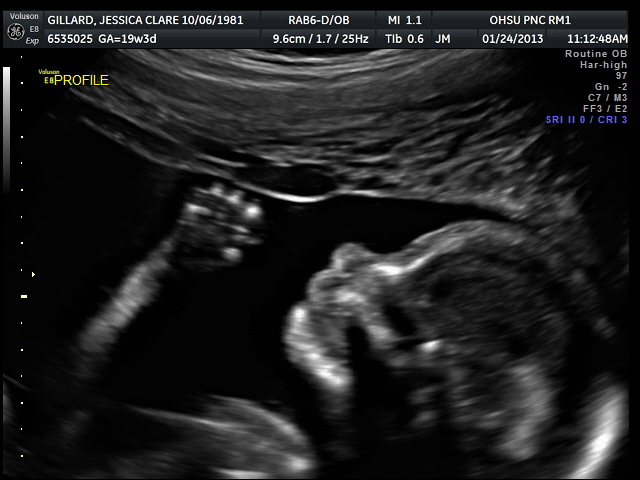

My parents got to attend the ultrasound, which was fun! Everything was normal except they never saw the stomach empty and wanted me to return in three weeks to look for that. I ended up deciding not to because I think I pay like $80 for the ultrasounds, I’m somewhat concerned about possible risks of too many ultrasounds, and I haven’t been able to figure out what sort of problem they’re actually concerned about and it sounds like there’s nothing that would be done before the birth if there is a problem, anyway. Also from what I’ve read it sounds like it might have been too early to necessarily see stomach emptying in the amount of time we were there. At my next prenatal visit, the midwife said she’d never seen that comment on an ultrasound report before and didn’t have any advice either way. So I’m just not going to worry about it! But I do wish I had asked more questions when I was there with the perinatologist who told me to go back. Live and learn…